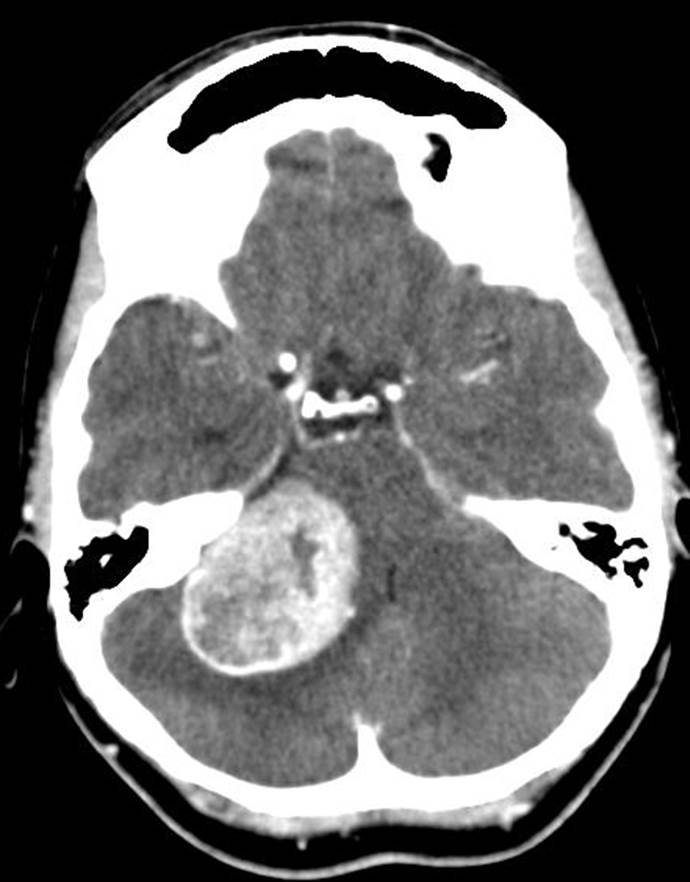

Caso 13

La TC craneal es una técnica no invasiva, sin efectos lesivos (salvo por la radiación absorbida por el usuario), que requiere poca colaboración del paciente (a diferencia de la Rx en que pequeños movimientos causan grandes distorsiones, la TC por sus secuencias rápidas y múltiples minimiza estas distorsiones) a la vez que nos brinda abundante información del cráneo, espacio extraaxial y parénquima del encéfalo. Pero sobre todo la TC es rápida y tiene una alta disponibilidad. Ante una situación de déficit neurológico, como la que se nos presenta, la TC está indicada como la técnica de elección. Además, se solicita un estudio con contraste para realzar lesiones, dado que la exploración clínica pone nos sobre sospecha de alguna lesión de tipo masa.